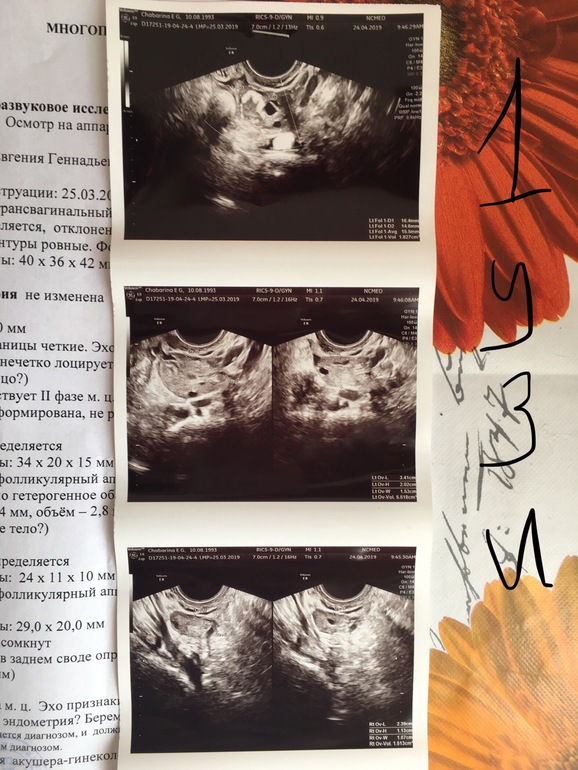

Вопросы про УЗИ, обследования и анализы: что, где, как, когда?Добрый день , я у вас новенькая ) задержка 2 недели , на первой недели была на узи и сейчас . При первом ставили маточную, сейчас внематочную . Помогите разобраться 🙏🏻😩 фото под катом .

Почему тогда на первом было в матке ? Даже целых 2 мм ? У нас в больнице такие врачи , что я сбежала оттуда с сохранения неделю назад . Записалась в другую клинику на завтра на узи

Вот на втором узи написано что что то около яичника 21 мм , разве мог так вырасти ?